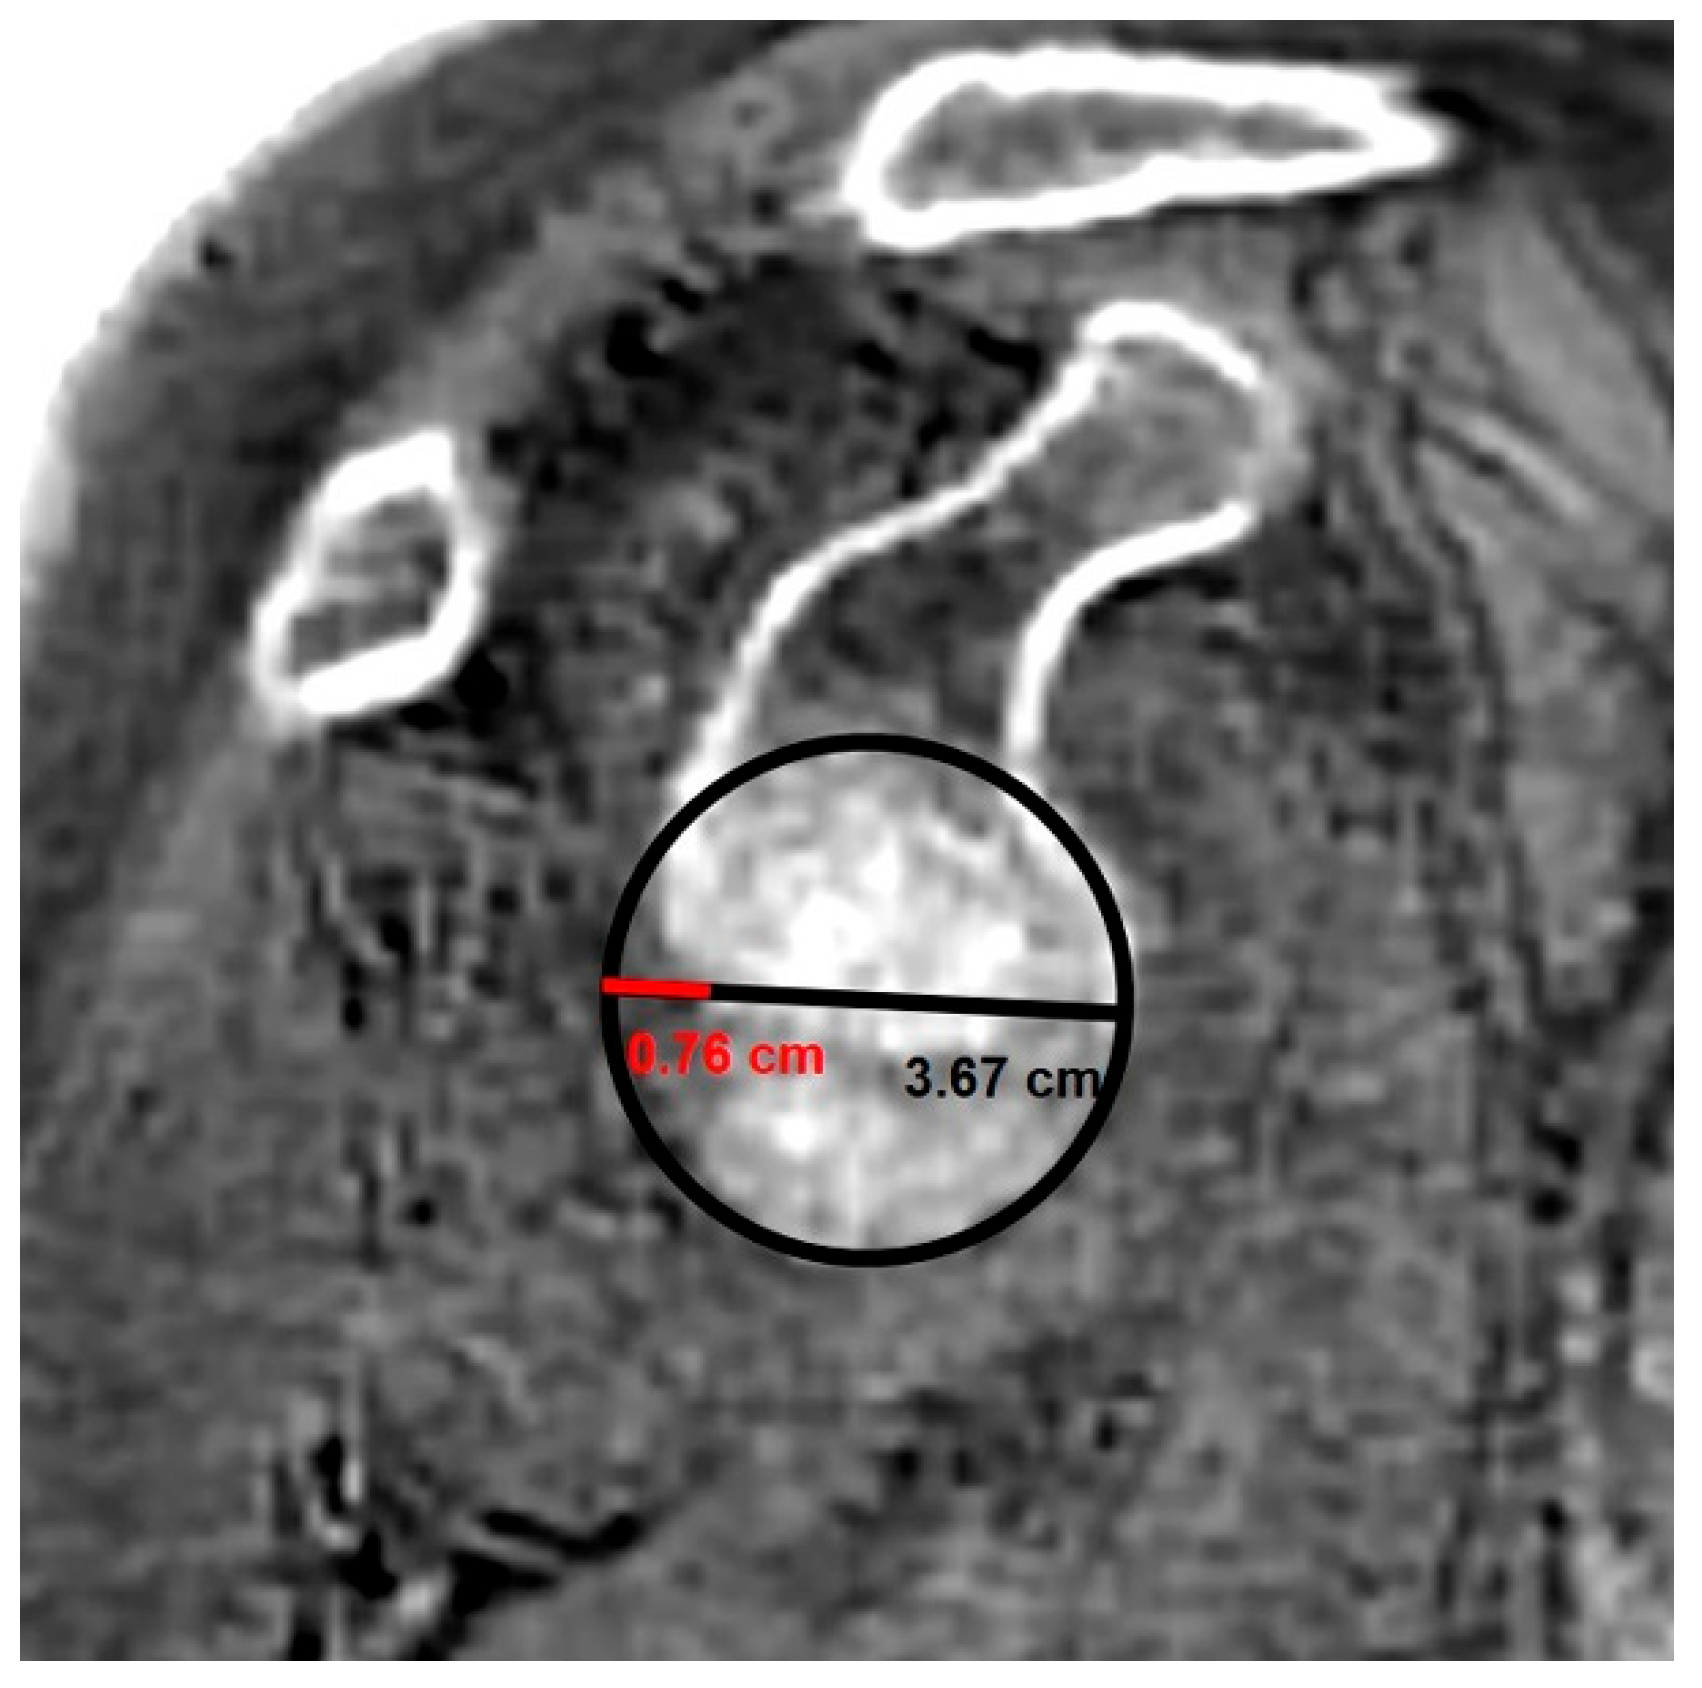

- MRI-based measurements

| Best-fit circle width | 0.863 | 0.746–0.926 | >0.05 | 0.828 | 0.619–0.916 | >0.05 |

| Glenoid best-fit circle bone loss ratio | 0.818 | 0.546–0.927 | >0.05 | 0.640 | 0.292–0.836 | >0.05 |